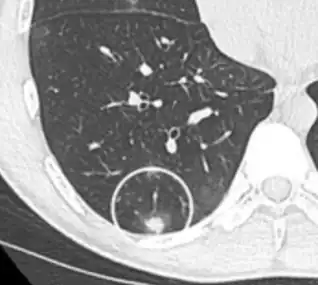

On chest X-ray and CT, pulmonary aspergillosis classically manifests as a halo sign, and later, an air crescent sign.[24] In hematologic patients with invasive aspergillosis, the galactomannan test can make the diagnosis in a noninvasive way. Galactomannan is a component of the fungal wall.[13] False-positive Aspergillus galactomannan tests have been found in patients on intravenous treatment with some antibiotics or fluids containing gluconate or citric acid such as some transfusion platelets, parenteral nutrition, or PlasmaLyte.[25][26]

On microscopy, Aspergillus species are reliably demonstrated by silver stains, e.g., Gridley stain or Gomori methenamine-silver.[27] These give the fungal walls a gray-black colour. The hyphae of Aspergillus species range in diameter from 2.5 to 4.5 μm. They have septate hyphae,[28] but these are not always apparent, and in such cases they may be mistaken for Zygomycota.[27] Aspergillus hyphae tend to have dichotomous branching that is progressive and primarily at acute angles of around 45°.[27]